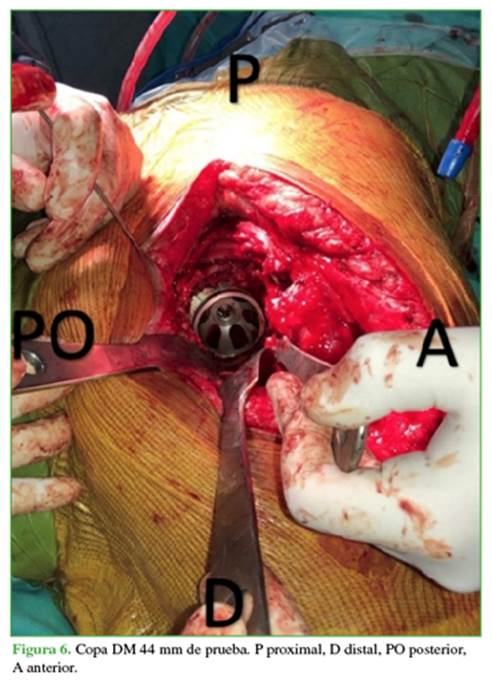

Se presenta un cotilo de prueba de 44 mm (Figura 6), se verifica que sus dimensiones permitirán dejar 2-3 mm para el manto de cemento, lo cual se corroboró previamente en la planificación prequirúrgica (Figura 7). Se utilizó cemento con antibiótico (gentamicina + vancomicina) para disminuir el índice de probabilidad de infección.